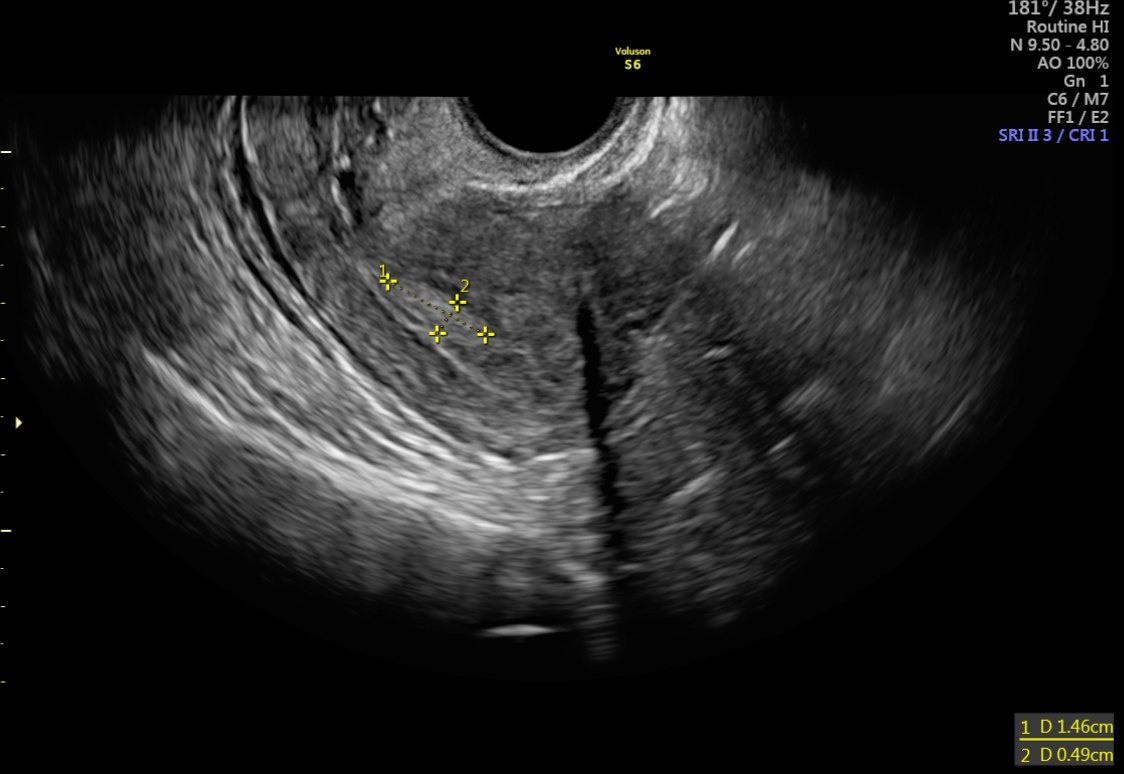

Для диагностики полипов эндометрия используются различные методы, включая ультразвуковое исследование (УЗИ), гистероскопию и биопсию. Гистероскопия является наиболее точным методом диагностики, так как она позволяет врачу визуально осмотреть полость матки и определить наличие полипов.